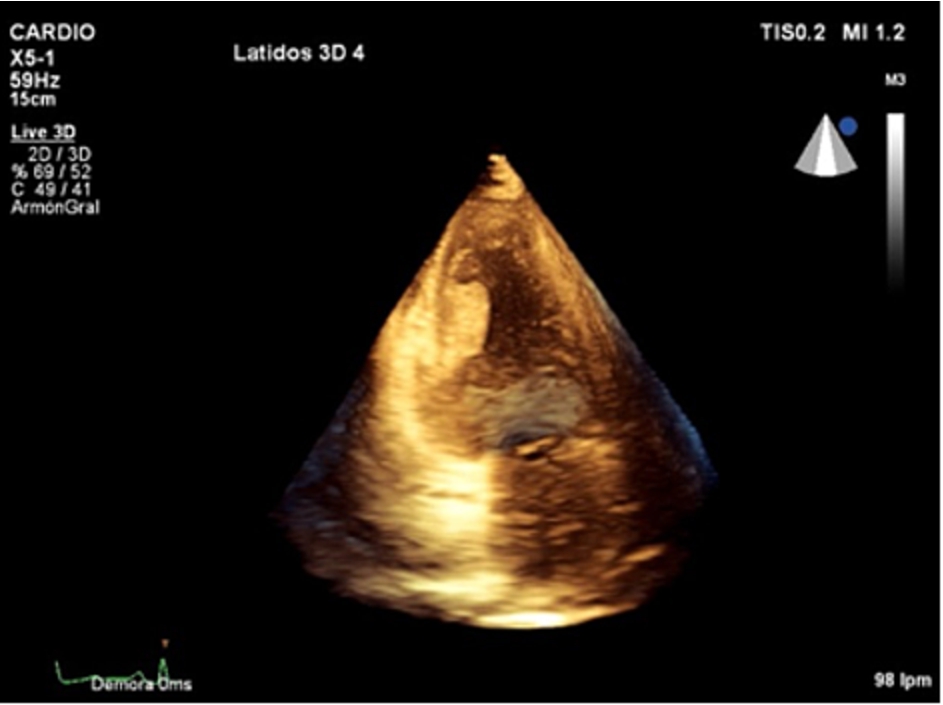

Figure 1.

Apical four-chamber echocardiographic view. Left ventricular mass attached to inferior interventricular septum.